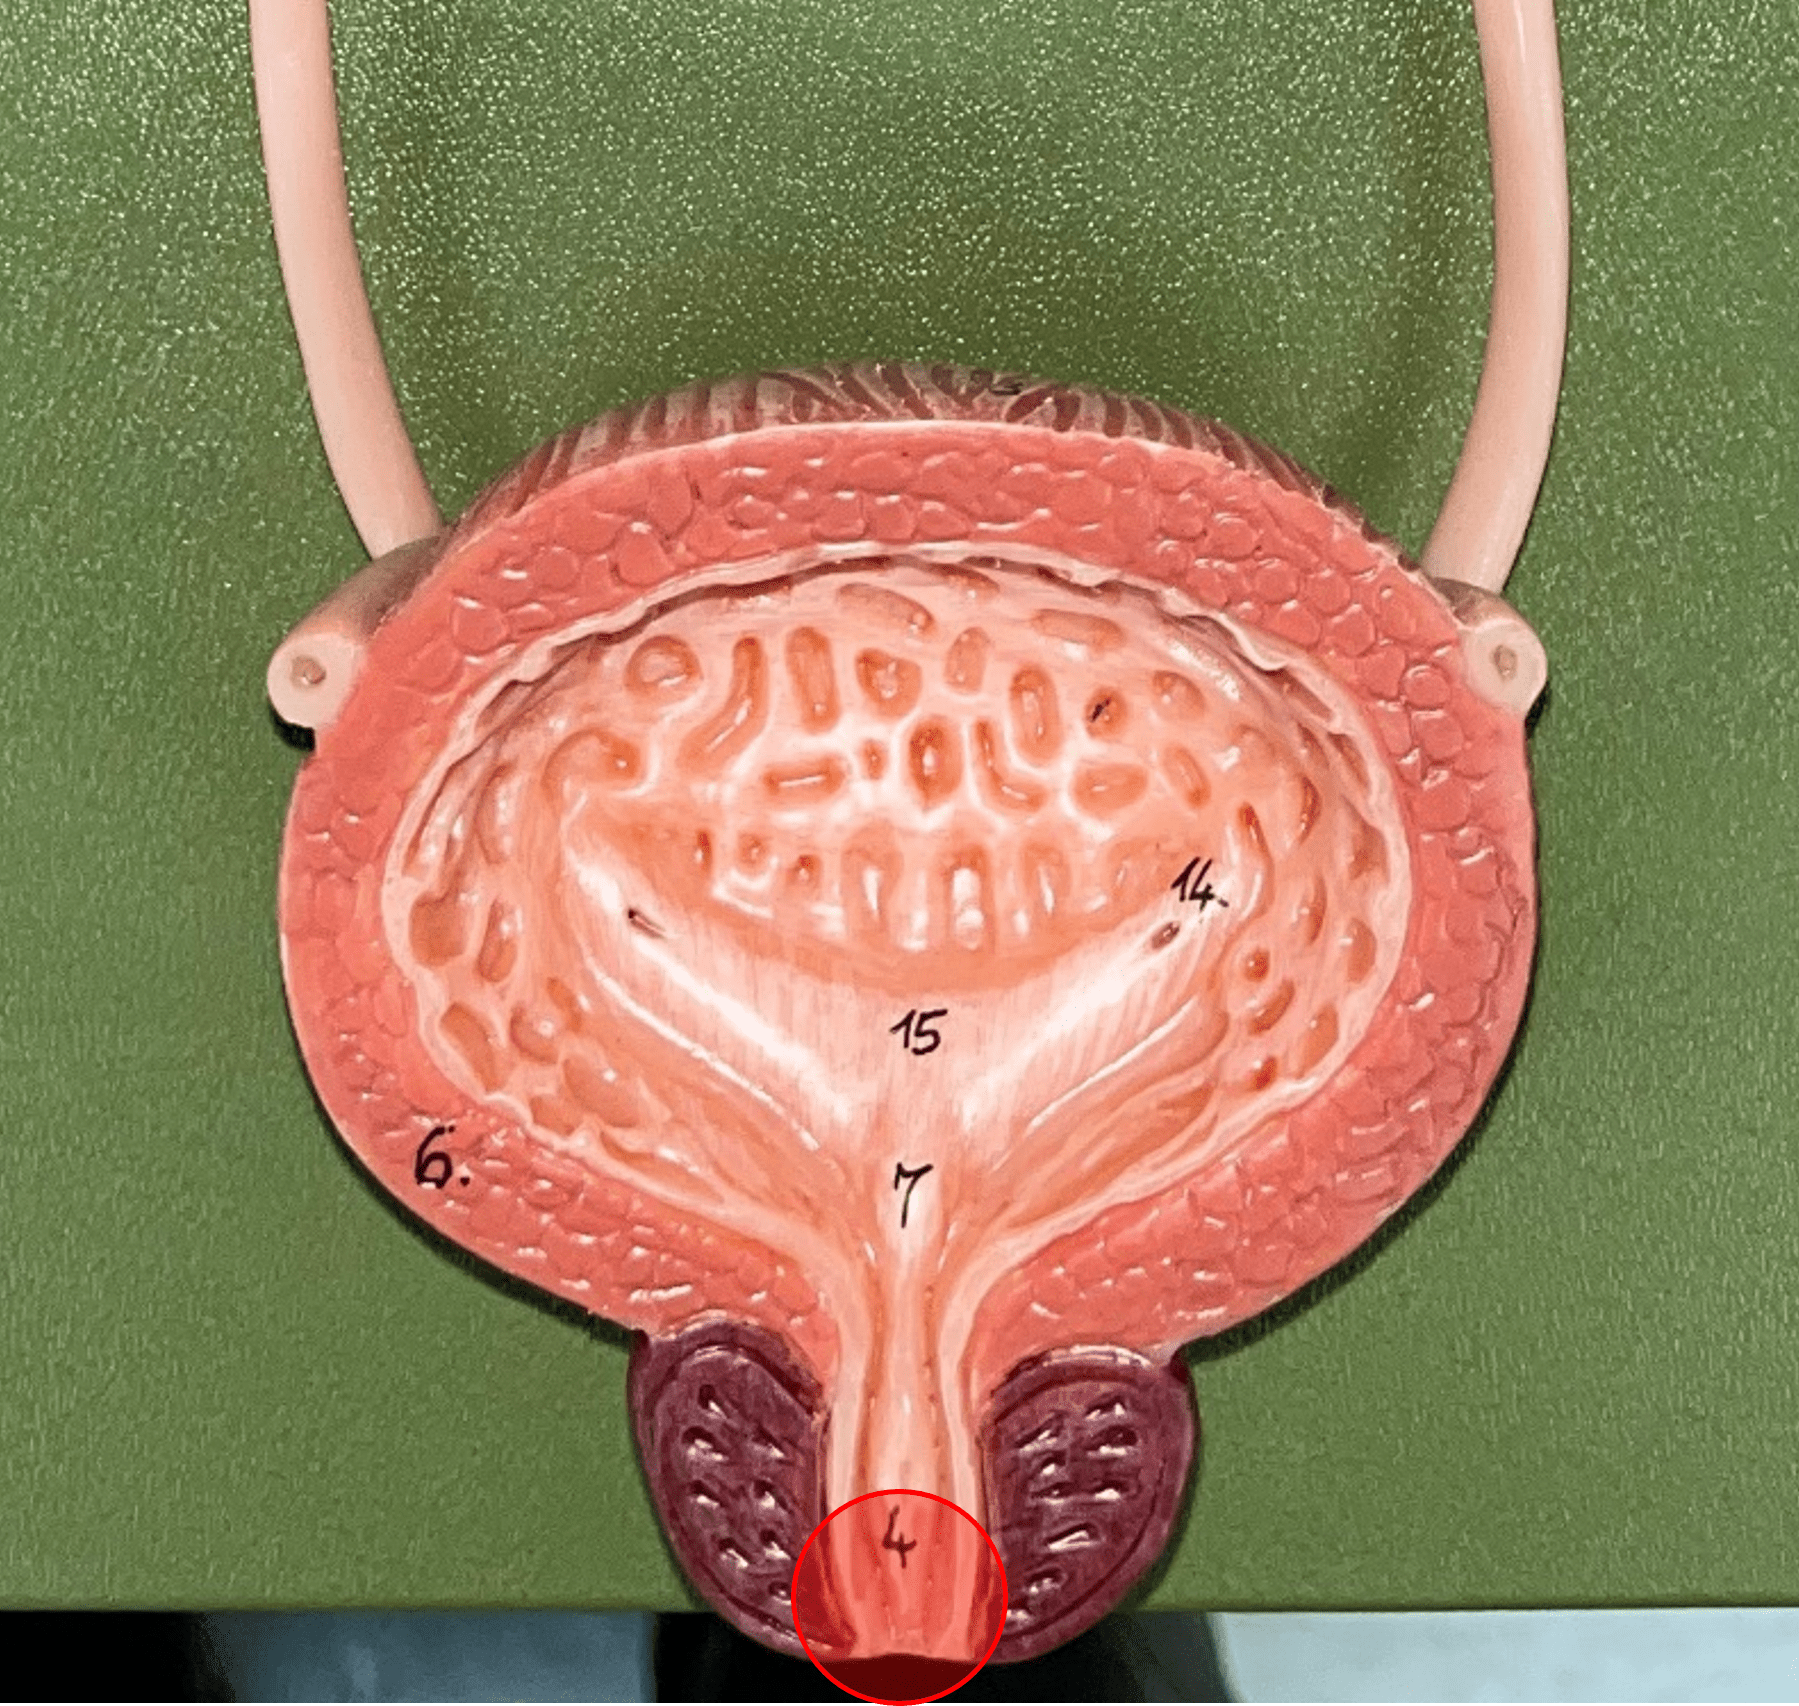

renal cortex

• The outermost region of the internal kidney.

• Superficial to the renal medulla.

• Appears slightly granular.

• Superficial to the renal medulla.

• Appears slightly granular.

5

New cards

renal medulla

• The middlemost region of the internal kidney.

• Deep to the renal cortex and superficial to the renal pelvis.

• Contains triangular renal pyramids.

• Appears striated due to the presence of tubules and ducts.

• Deep to the renal cortex and superficial to the renal pelvis.

• Contains triangular renal pyramids.

• Appears striated due to the presence of tubules and ducts.

6

New cards

renal pyramid

• A triangular structure found in the renal medulla.

• The base faces the renal cortex.

• The renal papilla (apex) faces the renal pelvis.

• The base faces the renal cortex.

• The renal papilla (apex) faces the renal pelvis.

7

New cards

renal papilla

The apex of the renal pyramid facing the renal pelvis.

8

New cards

renal column

An area of granular tissue (similar to the cortex) between renal pyramids.

9

New cards

minor calyx

• A cup-like extension that collect urine from the renal papilla.

• Converges with others to form a larger major calyx.

• Converges with others to form a larger major calyx.

10

New cards

major calyx

• The convergence of several minor calyces.

• Drains into the renal pelvis.

• Drains into the renal pelvis.

11

New cards

renal pelvis

• The innermost region of the internal kidney.

• Collects urine from the major calyces and drains it into the ureters.

• Includes the minor and major calyces.

• Collects urine from the major calyces and drains it into the ureters.

• Includes the minor and major calyces.

urinary bladder

The hollow sac organ that collects and temporarily stores urine.

rugae

• Part of the urinary bladder.

• Folds of the mucous membrane of the bladder.

• Flattens as the bladder fills with urine to increase capacity.

• Folds of the mucous membrane of the bladder.

• Flattens as the bladder fills with urine to increase capacity.

trigone

• Part of the urinary bladder.

• The triangle formed by the ureteral openings and internal urethra orifice.

• The triangle formed by the ureteral openings and internal urethra orifice.

ureteral opening

• Part of the urinary bladder.

• A posterior opening on either side of the of the bladder led in by the ureters.

• A posterior opening on either side of the of the bladder led in by the ureters.

internal urethral orifice

• Part of the urinary bladder.

• The anterior opening of the bladder leading to the urethra.

• The anterior opening of the bladder leading to the urethra.

detrusor muscle

• Part of the urinary bladder.

• The muscularis of the bladder.

• Contracts to expel urine from the bladder.

• The muscularis of the bladder.

• Contracts to expel urine from the bladder.

urethra

A tubular organ carrying urine from the bladder to the exterior during micturition (voiding of urine).

external urethral orifice

• Part of the urethra.

• The opening of the urethra to the exterior.

• The opening of the urethra to the exterior.

internal urethral sphincter

\

• Part of the urethra.

• A circular layer of circular smooth muscle located just after the internal urethral orifice.

• Involuntary muscle allowing urine to flow outward.

• Part of the urethra.

• A circular layer of circular smooth muscle located just after the internal urethral orifice.

• Involuntary muscle allowing urine to flow outward.

external urethral sphincter

• Part of the urethra.

• A layer of skeletal muscle located just before the external urethral orifice.

• Voluntary muscle allowing urine to flow out to the exterior.

• A layer of skeletal muscle located just before the external urethral orifice.

• Voluntary muscle allowing urine to flow out to the exterior.